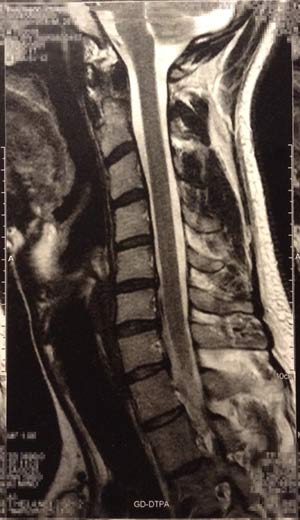

- montage.jpg

- Montage

- (28.02 KiB) 1777-mal heruntergeladen

zum Nackenbereich enthalte ich mich. Kernspinbilder sind noch

schwerer zu deuten als Röntgenbilder

Es fällt eine Steilstellung der HWS, eine leichte Hyperkyphose und eine leichte Skoliose auf und mit Schroth könntest Du wahrscheinlich ganz gute Ergebnisse erzielen.